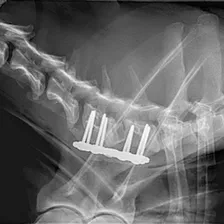

Spinal Surgery

Treatment of a wide range of spinal pathologies including intervertebral disc disease in the neck and back i.e. a ruptured or "slipped" disc, vertebral fractures and luxations & congenital disease e.g. atlantoaxial instability.